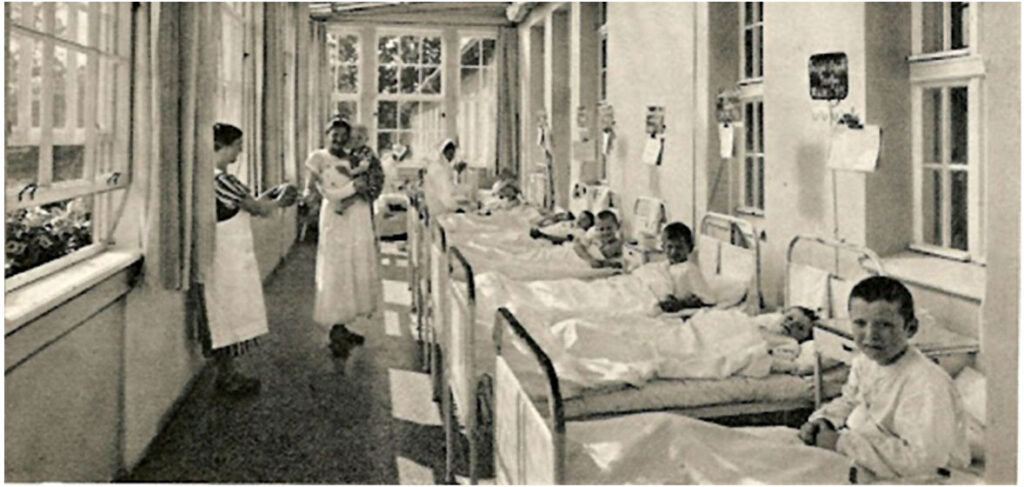

Słyszałam że w latach siedemdziesiątych użyto dobrych bakterii do leczenia dzieci w czasie epidemii czerwonki. Czy to prawda?

Tak, to prawda. „W 1972 r. doktor Zychowicz i doktor Cieplińska w lecznictwie pediatrycznym zastosowali po raz pierwszy fermentowany preparat mleczny do leczenia dzieci w czasie wieloletniej epidemii czerwonki w Państwowym Domu Małych Dzieci w Mrągowie, bezskutecznie poddanych wcześniej zaostrzonemu reżimowi sanitarnemu i leczonych za pomocą dostępnych środków farmaceutycznych. Preparat zawierał kulturę Lactobacillus acidophilus i nazwany był umownie mlekiem acidofilnym.

Fermentowany preparat mleczny podawano początkowo w niewielkich ilościach dobowych (20 – 150 cm3 w dawkach podzielonych), uzyskując niewielką poprawę, wyrażającą się ustąpieniem objawów jelitowych przy dodatnich jeszcze wynikach posiewów. W drugiej połowie 1972 r. zwiększono ilość mleka acidofilnego do 60 – 600 cm3 , podawanych w 2 – 3 dawkach dziennych.

W okresie stosowania kultury bakteryjnej (fermentowanego mleka) dzieciom nie podawano żadnych środków przeciwbakteryjnych. Wykonywane systematycznie posiewy najczęściej już po 2 – 3 tygodniach były ujemne. Pod koniec 1972 r. u wszystkich dzieci w Zakładzie, jak również u personelu posiewy były ujemne. Na szczególne podkreślenie zasługuje fakt obserwowanych zmian w stanie zdrowotnym dzieci.

Pod wpływem zastosowanego leczenia dietetycznego stwierdzono nie tylko ustąpienie objawów jelitowych i całkowite unormowanie wyników posiewów, ale zmiany w zachowaniu się dzieci, które stały się żywotniejsze, poprawił się ich apetyt, stały się bardziej odporne na infekcje wirusowe dróg oddechowych, poczyniły wyraźne postępy w rozwoju psychomotorycznym.”

(ŻYWNOŚĆ. Nauka. Technologia. Jakość, 2010, 4 (71), 5 – 19)